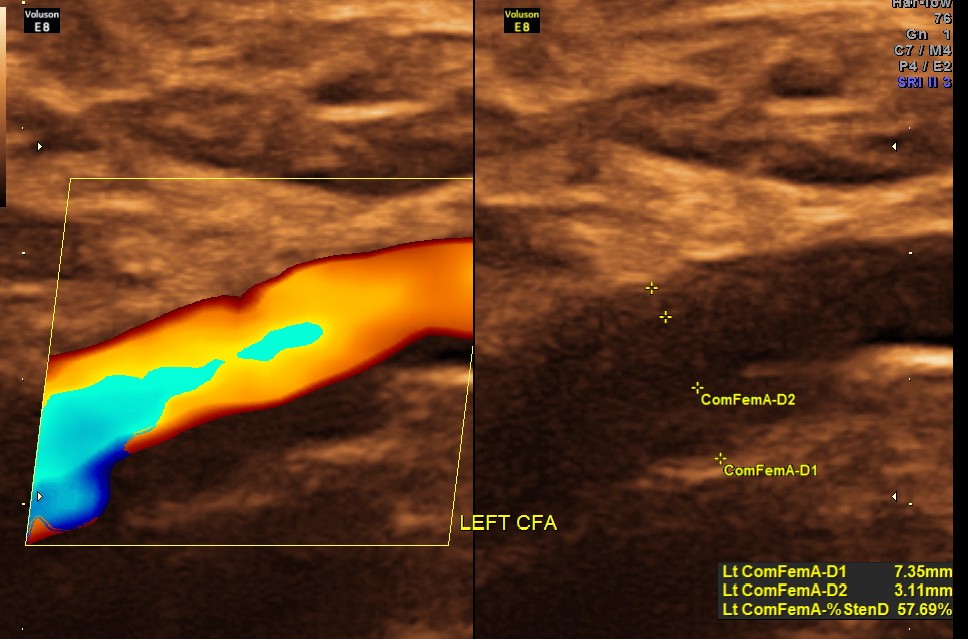

EXTENSIVE ATHEROSCLEROTIC OBSTRUCTIVE DISEASE OF THE LOWER LIMB ARTERIES WAS SEEN WITH THE CHANGES IN THE RIGHT COMMON FEMORAL ARTERY BEING MORE THAN THE LEFT CFA.